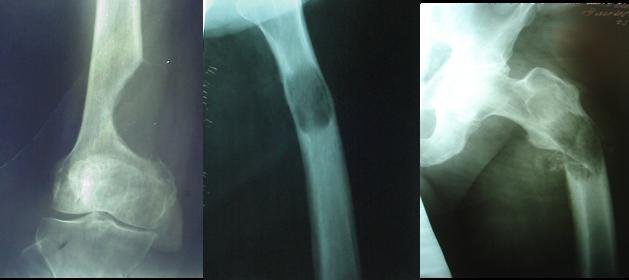

При раке легкого или груди чаще всего метастазы поражают костную ткань грудного отдела, матки и простаты – тазобедренных костей. В этом случае нужно подобрать травы, содержащие кальций, кремний и укрепляющие костную систему.

Три недели назад сломала шейку бедра бабушка 72 лет из соседнего подъезда. Года три назад такая же история произошла с нашем сторожем в детском саду. После этого она уже больше не встала… Неужели мы не можем ничем себе помочь, чтобы защитить свои кости от переломов?